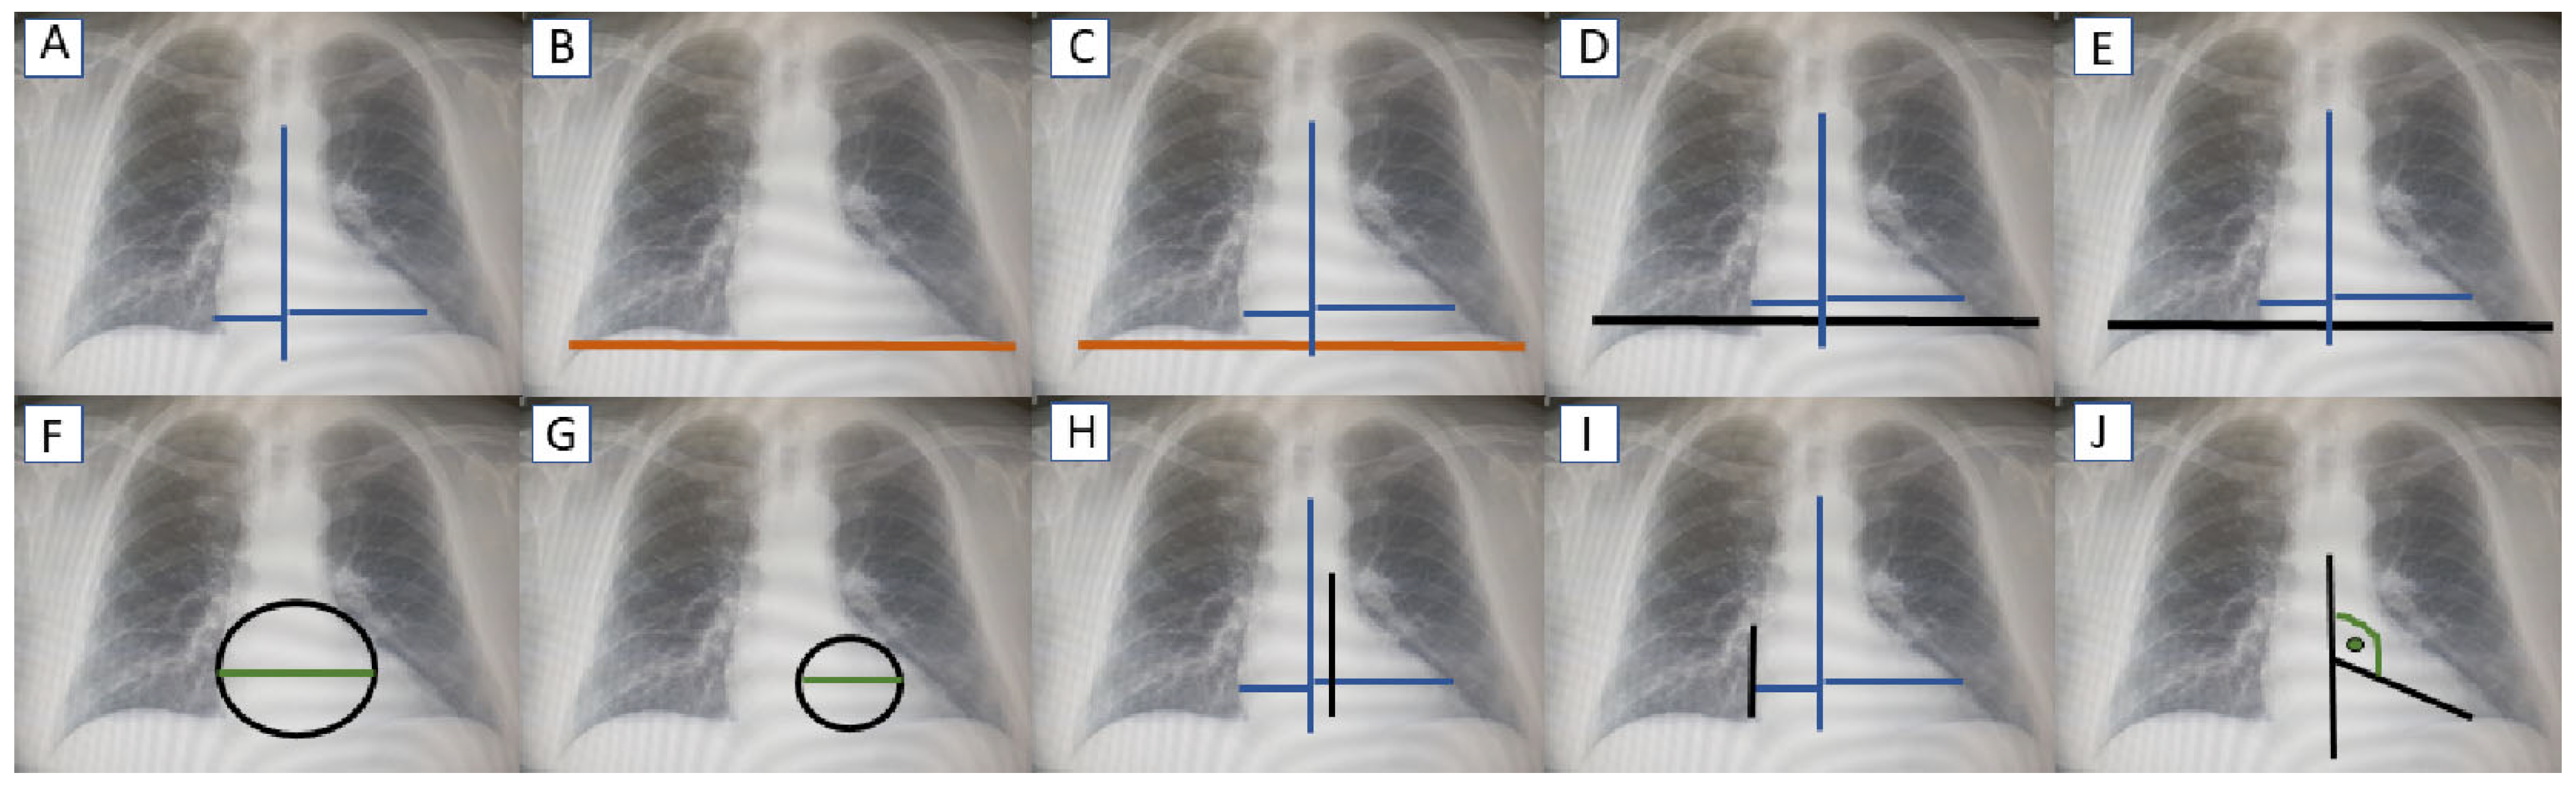

| Indexes | Definition |

|---|---|

| TCD | The transverse cardiac diameter was measured on the posterior–anterior film by drawing a vertical line through the vertebral bodies and calculating the sum of segments drawn perpendicular from the midline to the farthest edge of the cardiac silhouette in both directions. |

| TCHD | The greatest horizontal distance between the inner borders of the ribs with the chest in the mid-inspiratory position. |

| CTR 1 | TCD/TCHD |

| CTR 2 | TCD/horizontal distance between the inner borders of the ribs with the chest in the mid-inspiratory position at the level of the right diaphragm. |

| CTR 3 | TCD/horizontal distance between the inner borders of the ribs with the chest in the mid-inspiratory position at the level of the left diaphragm. |

| BSI | The BSI represents the diameter of a theoretical circle to which both the left and right heart contours are tangent. It provides a metric for the assessment of changes in the cardiac silhouette that occur with LV enlargement. Clinically, the BSI is significant as it reflects not only the transverse diameter but also the overall shape of the heart, offering a more nuanced perspective than traditional measurements such as the CTR. |

| LSI | The LSI quantifies the diameter of the circle tangent to the left-most convex contour of the heart. This index focuses on the left heart border, which is more prominently affected in cases of LV enlargement, making it particularly relevant for evaluating asymmetric cardiac enlargement. |

| LDR | The LDR is calculated as the ratio of the distance between the lower wall of the left bronchus and the left diaphragm to the TCD. This index highlights structural changes in the lower left region of the cardiac silhouette, which often occur in LV dilatation. |

| RDR | The RDR evaluates the diameter of the line connecting the upper visible right heart contour to the right diaphragm, normalized to TCD. While primarily used for symmetry assessment, this parameter can help differentiate between right- and left-sided cardiac contributions to overall enlargement. |

| IA | The IA measures the angle formed by the largest oblique diameter of the heart toward the apex and a central horizontal line. This index reflects apex displacement due to left ventricular enlargement and helps to identify changes in the orientation of the cardiac silhouette. |